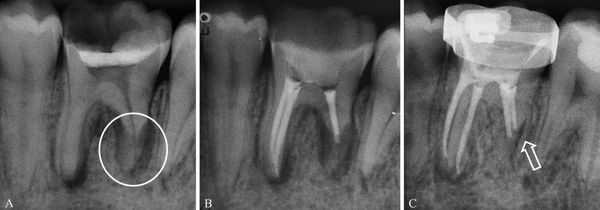

- Поперечные. Линия разлома проходит параллельно жевательной поверхности. На рентгенограмме удается рассмотреть 1-2 полоски просветления, соответствующие уровню повреждения.

При косых медио-дистальных переломах корня зуба, а также в случае, когда линии перелома перпендикулярны рентгеновскому лучу, обнаружить разлом корня с помощью прицельной рентгенологической диагностики довольно сложно. Для уточнения характера патологии проводят КТ. При горизонтальных, вертикальных вестибуло-оральных переломах корня зуба на рентгенограммах выявляют расширение периодонтальной щели. Зона разрежения костной ткани в виде тонкой полоски просветления проходит в участке повреждения. При позднем обращении пациентов рентгенографически в проекции перелома корня зуба определяют участок деструкции кости с нечеткими контурами, наблюдаются признаки резорбции корня. Прицельную рентгенографию проводят дважды: в момент травмы и через неделю.

Тактика врача при переломе корня определяется характером и локализацией повреждения, возрастом пациента, уровнем смещения фрагментов. При выявлении поперечного перелома апикальной трети с нарушением витальности пульпы проводят экстирпацию коронковой и корневой пульпы, медикаментозную и механическую обработку каналов с последующим их пломбированием временной кальцийсодержащей пастой. После обтурации корневых каналов методом латеральной или вертикальной конденсации гуттаперчи производят хирургическое вмешательство, цель которого при переломе корня зуба заключается в удалении отломанного апикального фрагмента. При сохранении витальности пульпы показана иммобилизация зуба специальной каппой или проволочной шиной, зафиксированной к 2 интактным зубам по обе стороны от поврежденного с помощью жидкого фотополимерного материала.

Если при поперечно-срединном переломе корня необратимых изменений в пульпе не наблюдается, чтобы обеспечить необходимые условия для сращения фрагментов, применяют каппу, стекловолоконную или проволочно-композитную шины. В случае выявления признаков нежизнеспособности пульпы терапия перелома корня зуба включает этап эндодонтического лечения, установку штифта с репозицией, фиксацией, иммобилизацией отломков. При вертикальном или косом переломе однокорневые зубы подлежат удалению. В случае разлома одного из корней моляров или премоляров выполняют зубосохраняющие операции. При гемисекции зуба через жевательную поверхность по бифуркации в щечно-оральном направлении бором разрезают коронку. Поврежденный корень удаляют. Сохранившийся здоровый корень используют в качестве опоры при протезировании. Выявление разлома корня временного зуба является прямым показанием к его удалению.